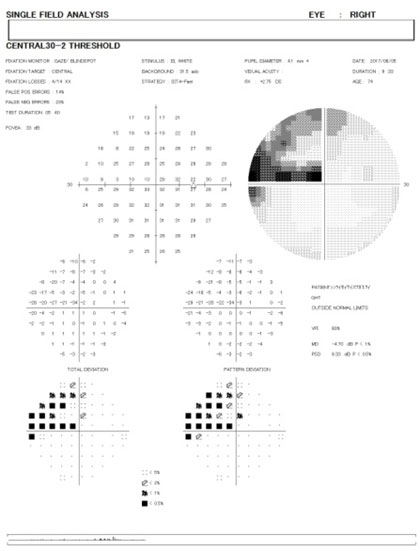

従来から緑内障の早期発見と点眼治療開始時期を決める為の検査としては、 主として眼底カメラ、眼圧検査、前房隅角検査、ハンフリー視野検査等の経過を総合的に判断して診断されて来ました。 特に視野が正常かそれとも異常が現れて来たかは、今でも非常に重要な判断材料とされています。

最近この判断を助ける上での画期的な検査機器が登場しました。眼底三次元画像解析装置(OCT)とよばれるもので、近赤外線レーザーを用いて眼底の視神経乳頭の変化や網膜視神経線維層の厚みの変化を正確に判定出来るようになったのです。当院はOCTをいち早く導入し、緑内障を示唆する異常がありながらも、通常の視野検査でまだ視野欠損を認めない状態である前視野緑内障(preperimetric glaucoma:PPG)を検出することができます。緑内障は早期発見早期治療が基本ですので、超早期緑内障の治療を早期に発見をして経過観察を行っていくことは、緑内障の患者様にとって大切であると思っております。

緑内障患者様において視野障害が現れた時点では、すでに5〜6割以上の視神経障害を受けている事が分かってきました。緑内障による視野異常は現時点では回復させる方法がありません。 予防医学の観点から視野異常が出る前の前視野緑内障から点眼治療を開始した方が、その患者さんの人生の生涯の視機能の質を維持する事が出来ると考えております。

緑内障の早期発見の為に、特に前視野緑内障の検出に非常に有用なOCT検査を精密視野検査やその他の検査と併せて行っております。ドックや健診で乳頭陥凹と指摘された方は勿論、近視の強い方や、家族に緑内障患者さんがおられる方は特に早めの検査を受けるようにお勧めしております。病状によりハンフリー視野検査 ゴールドマン視野検査 視神経乳頭解析 GCAを3〜6ヶ月に行い、進行をグラフ化して経過観察を行います。